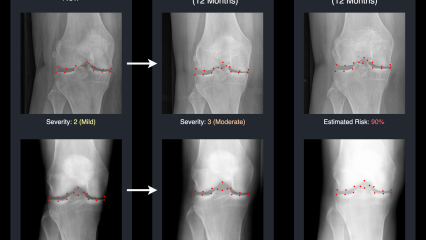

Supervised by PAI and CVSSP’s Professors Adrian Hilton and Gustavo Carneiro, PhD researcher David Butler has produced an important paper on how AI can improve osteoarthritic knee care. This is an important leap towards more personalised, anticipatory care, using AI not just to predict but to communicate future health states in a proactive way. The paper has recently been accepted to MICCAI, the leading medical image analysis conference, as being in the top 9% of the submissions, a huge accomplishment in itself.

But the researchers see the potential effect on patient outcomes as their greatest achievement.